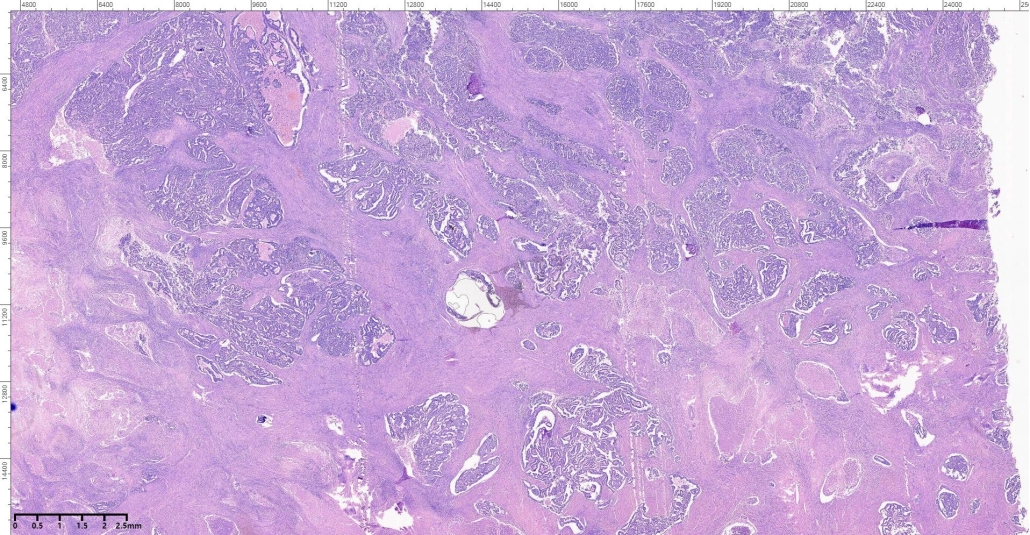

A 65-year- old female presented with vaginal bleeding. On radiological examination there was a diffuse thickening of endometrium. Patient underwent total abdominal hysterectomy and bilateral salpingo ophrectomy. On gross examination there was a grayish white mass involving the uterine cavity.